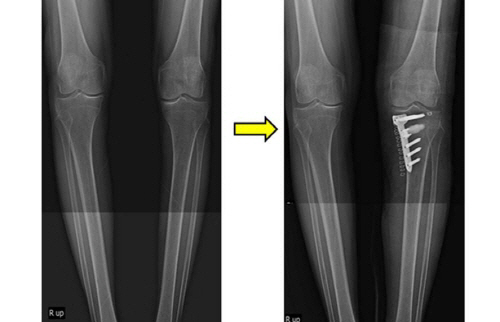

A :퇴행성관절염에 시행되는 근위경골절골술은 경골의 내측에서 변형이 필요한 만큼 절골하여 개방시킨 후 금속물로 고정하고 골이식을 하는 수술이다. 무릎은 세개의 구역으로 나누는데 내측, 외측, 슬개대퇴 구획으로 나뉜다. 대게 무릎의 관절염 환자들은 한 구획을 침범하는 경우가 많으며 대부분 내측의 침범이 많다. 이런경우 하지의 정열을 재조정하여 체중부하를 아프지 않은 쪽으로 옮겨서 통증을 줄이고 관절염의 진행을 늦추고 회복되도록 도움주는 방법이 근위경골 절골수술이다.